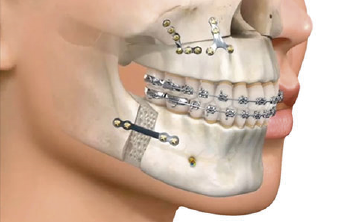

Es la rama de la odontología encargada del diagnóstico y tratamiento quirúrgico de las alteraciones en los tejidos duros y blandos de la boca como patologías infecciosas, tumorales y de malformaciones bucales y maxilofaciales, utilizando como ayudas diagnósticas la imagenología, la histopatología y pruebas de laboratorio clínico.

El odontólogo especialista en esta área posee el conocimiento y la destreza para toma de biopsias, realización de tratamientos de urgencias, manejo de alteraciones de la boca como: frenillos traccionantes, dientes retenidos o incluidos, cirugías pre protésicas, cirugías maxilo facilaes y reconstructivas.